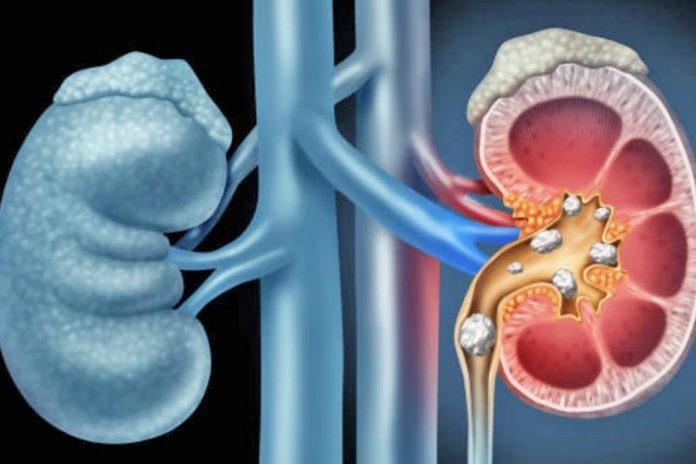

Veshkat janë përgjegjëse për eliminimin e mineraleve të ndryshme nga gjaku, nëpërmjet urinës.

Në shumë raste, sasi të larta mineralesh akumulohen në veshka duke formuar gurë.

Kur gurët janë të vegjël ato dalin nga trupi me më shumë lehtësi.

Kur gurët janë të mëdhenj ato ngecin në kanalin që lidh veshkën me fshikzën e urines dhe shkaktojnë dhimbje.

Një gjë e tillë shkakton edhe infeksion apo dëmtim të veshkave.

Gurët mund të formohen në fillim të kanalit të sipërpërmendur ose në pjesën fundore të tij që është pranë fshikëzës.